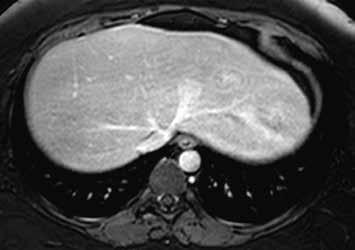

Již nativně jsou na T1-váženém obraze vidět vícečetná hyperintenzní ložiska (7). V arteriální fázi ložiska zůstávají hyperintenzní (8), v portovenózní fázi (9) a v hepatospecifické fázi (10) postupně splývají s okolním parenchymem.

Nativně je v jaterním parenchymu naznačeno několik minimálně hyperintenzních ložisek (13). Ložiska se zvýrazňují ve fázi arteriální (14) i portovenózní (15). V hepatospecifické fázi jsou nadále hyperintenzní (16).